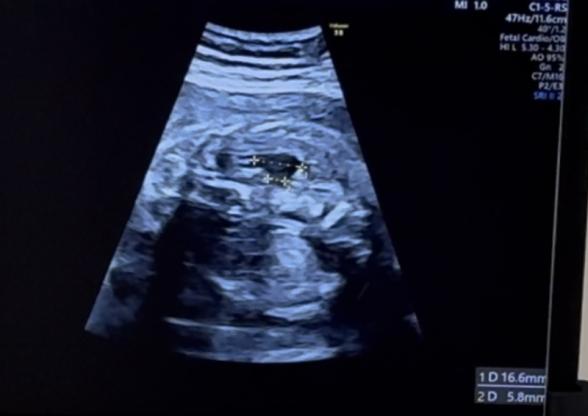

26w5dの健診で、初めて右側の腎臓が腫れているから、水腎症かもしれないと言われました。

エコー写真がその時のサイズです。

上の方が16.6mm、下の方が5.8mmになっています。

chatgptに聞いたところ、下の方が腎盂の大きさの可能性があり、5.8mmは軽度ではないかとのこと。